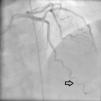

Medicina Clínica Spontaneous coronary artery dissection: Not so infrequent to be ignored

Spontaneous coronary artery dissection: Not so infrequent to be ignored

Disección coronaria espontánea: no tan infrecuente para ser ignorada